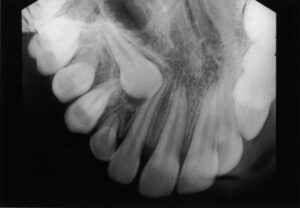

They come in between the ages of 17 and 25. When a tooth is unable to fully enter the mouth, it is said to be “impacted.” In general, impacted teeth are unable to break through the gums because there is not enough room. Nine out of ten people have at least one impacted wisdom tooth.

Impacted inside the jaw